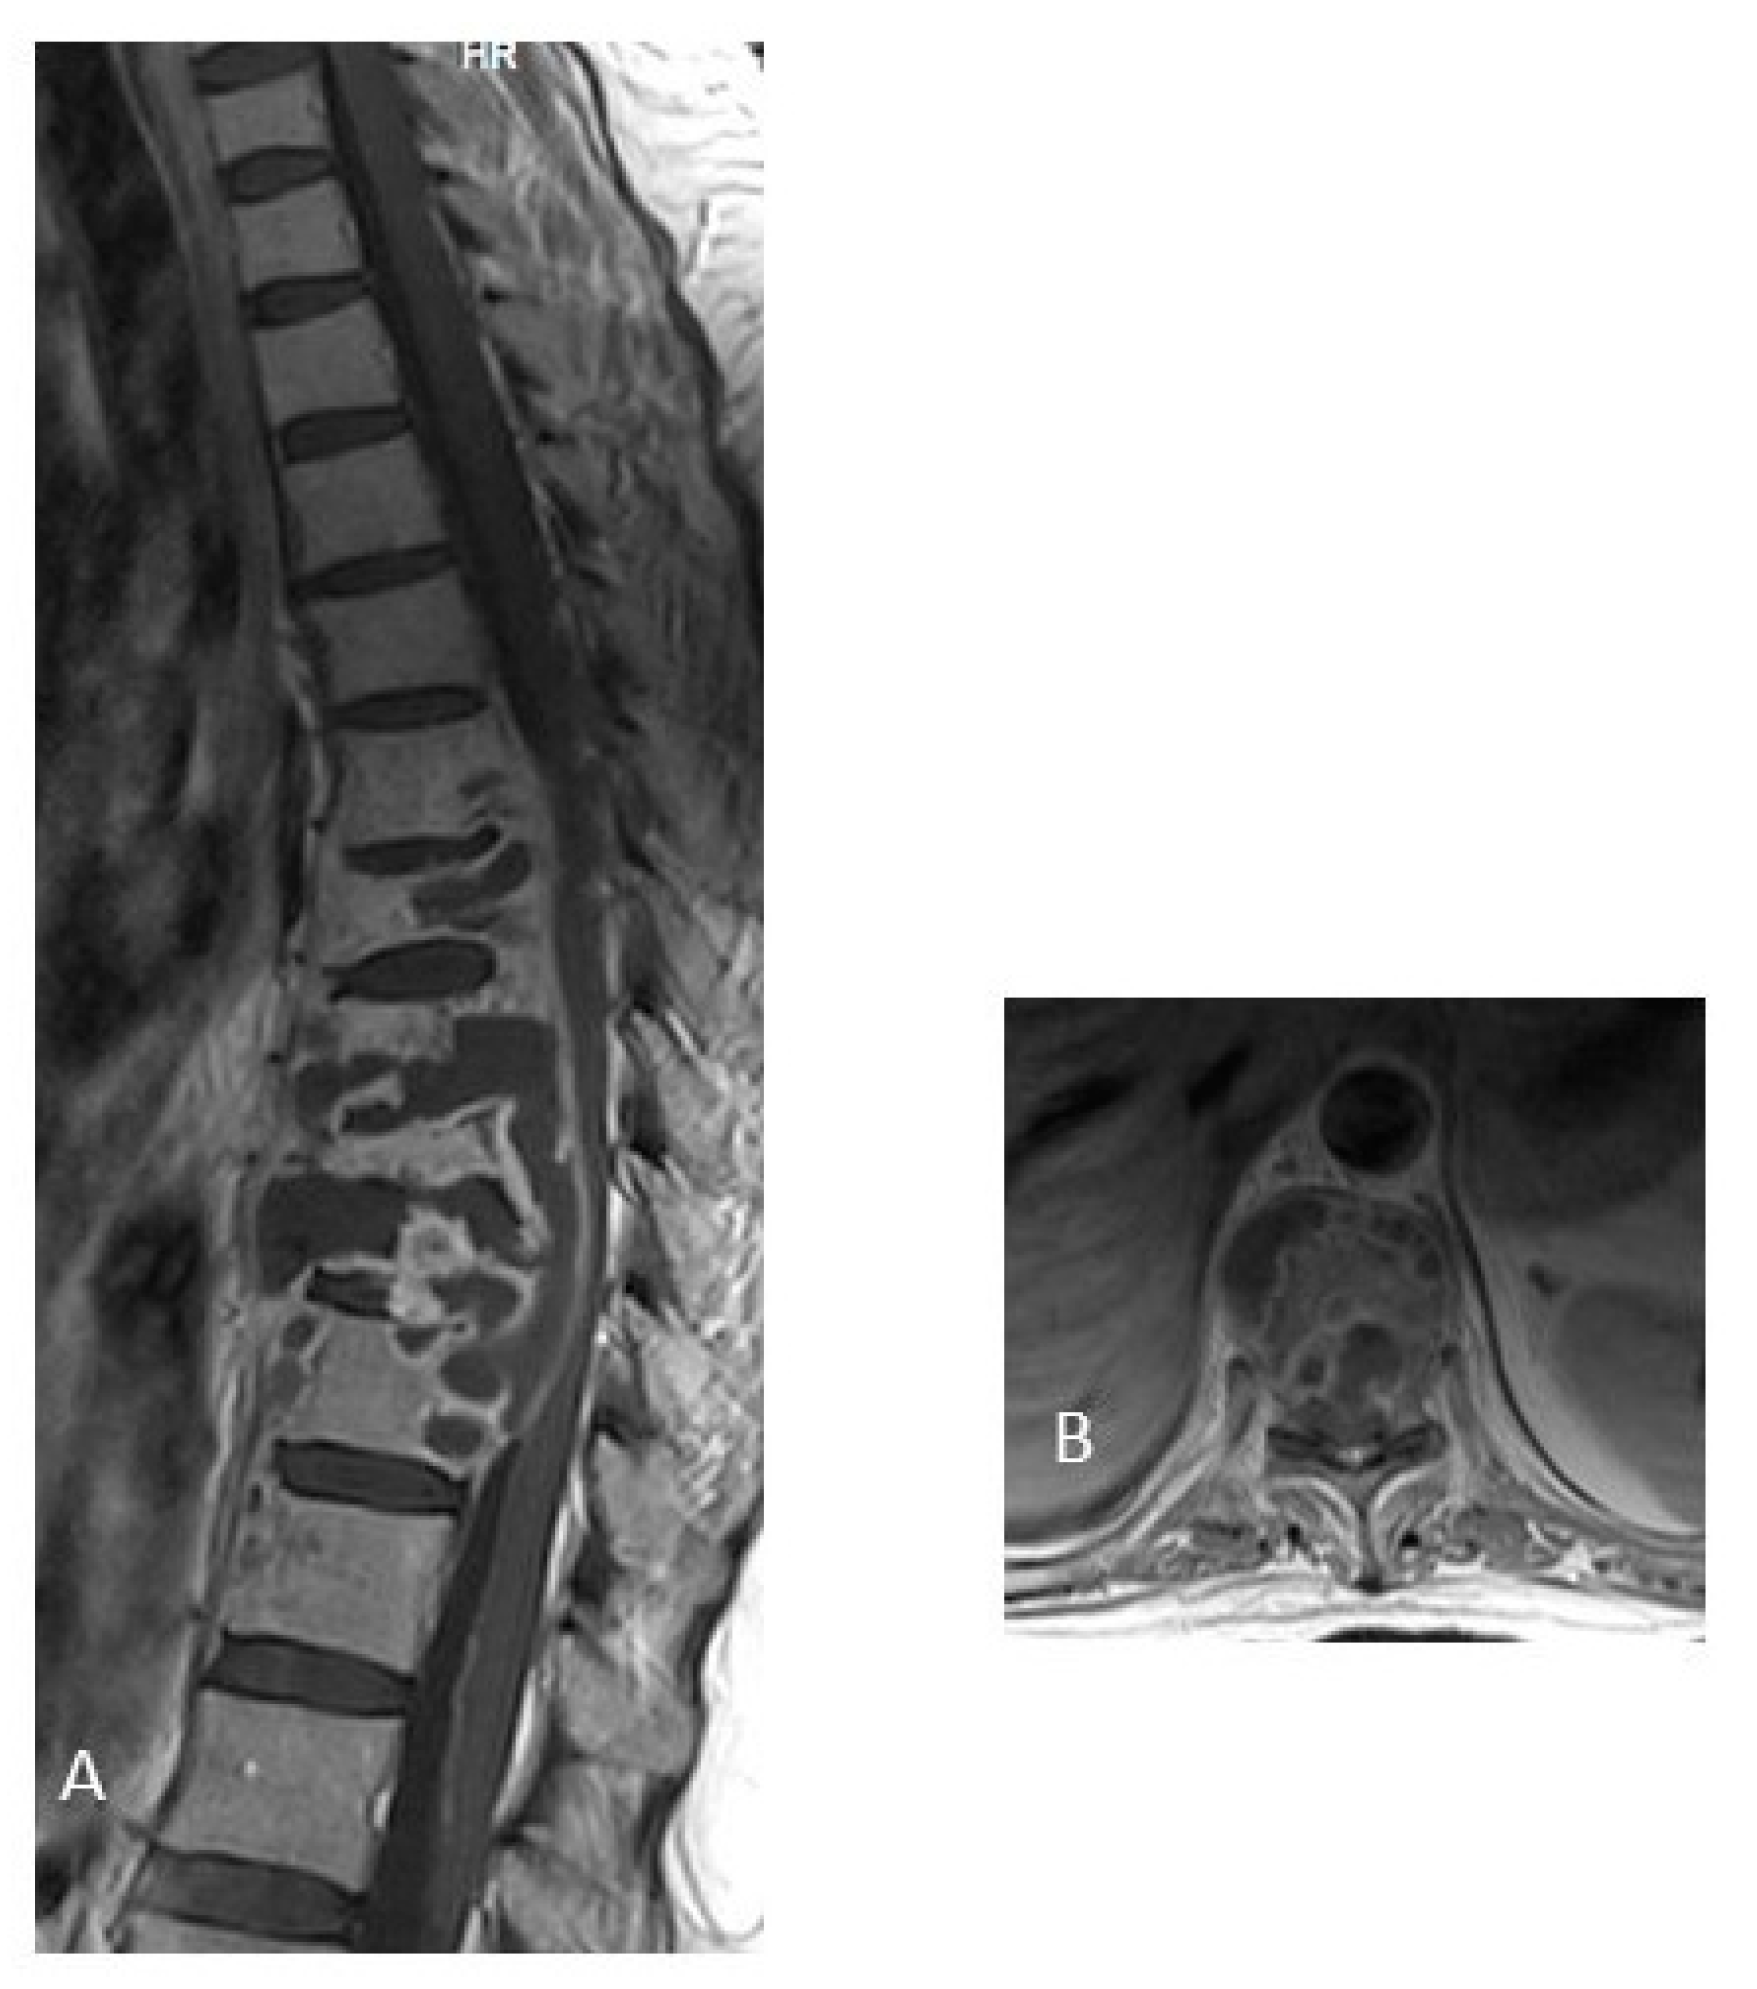

3.1. Intraspinal NeuroTB

4.1. Intraspinal NeuroTB